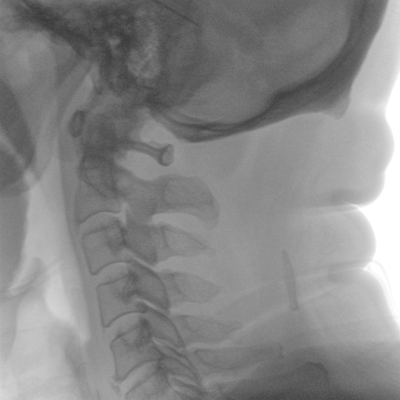

在球管和平板探測器兩端,分別加裝了激光定位系統,滿足不同擺位無射線下的定位需求,降低醫患輻射劑量的同時,提高臨床工作效率。

具備束光器預覽功能,可以在無射線狀態下,實現曝光范圍大小的調節;大幅減少臨床反復曝光帶來的射線輻射;并自動調整圖像興趣區大小與位置,使自動模式更準確。